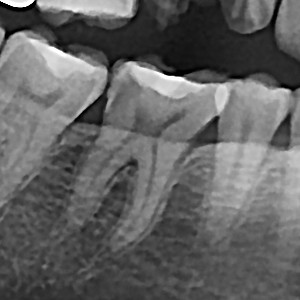

충치치료&신경치료 하루에 끝나는 신경치료

60bab75a1a70db4a6fd0ef2b4df1f9ae_1767344664_5778.jpg